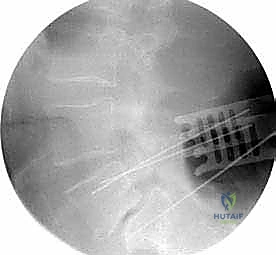

* الأشعة السينية (X-rays): خاصة الصور الديناميكية (أثناء الانحناء للأمام والخلف) لتقييم درجة عدم الاستقرار الميكانيكي والانزلاق.

* التصوير المقطعي المحوسب (CT Scan): يوفر صوراً ثلاثية الأبعاد للعظام، وهو ضروري جداً للتخطيط الجراحي الدقيق وتحديد أحجام المسامير المناسبة لكل سويقة فقارية.